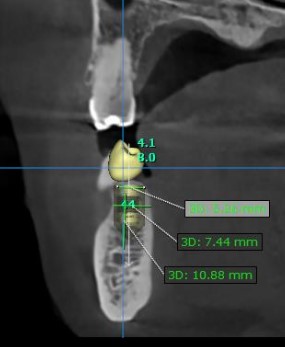

Good morning everyone, I would like to get your opinion on the following treatment options for this case. This patient has missing 47, 46 and a retained root at 45. Interocclusal space is about 5mm ( so i cannot perform vertical bone augmentation), bone height is limited, about 10mm ( close proximity to ID canal) and bone width is not satisfactory as well . I have not used any short implants with high engaging threads ( BLX implant) in my practice so I would like to get everyone’s input on this. Thank you.

Treatment plan 3 units straumann BLT implant (45 : 4.1mm x 8mm, 46 : 4.1mmx8mm, 47: 4.8mmx8mm) + GBR with autogenous and straumann xenograft + 2 units splinted 46,47 and single unit 45 final prosthesis

– Concern – Longer implants but near to ID canal, about 1-2mm away if place implants at the same level at bone crest and limited/abscence of buccal bone